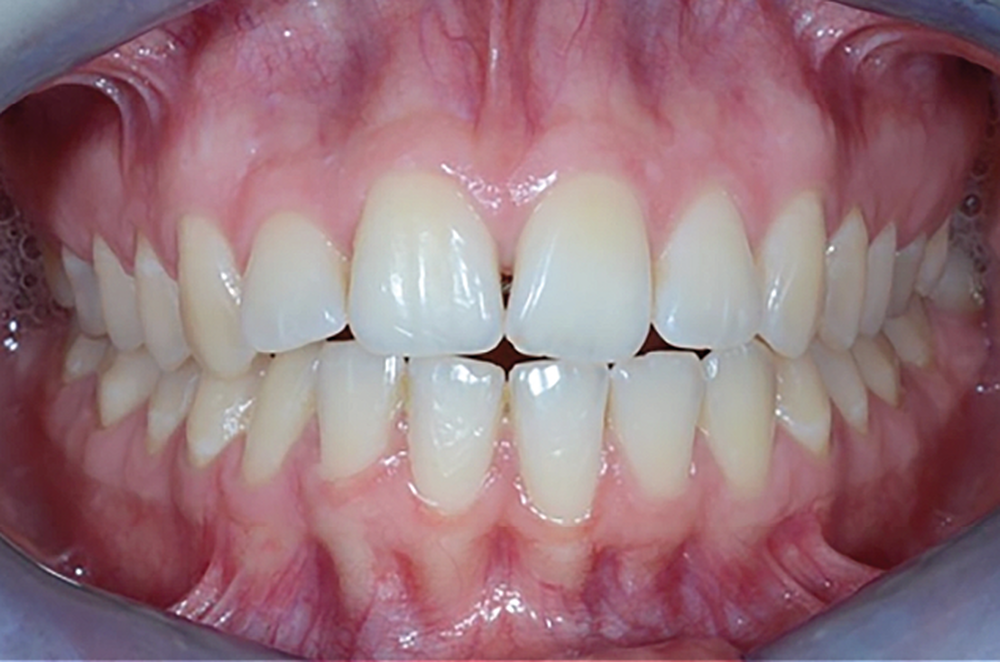

Le Pr Olivier Sorel insistera sur l’importance du respect des formes et des proportions anatomiques, pour éviter de voir apparaître, notamment chez les adultes, de très inesthétiques triangles noirs lors de la phase d’alignement (fig. 6a-b). Il présentera sa démarche diagnostique (évaluation de la forme des dents et de la dysharmonie dento-dentaire, fig. 7a-c) et l’intégration de la réduction amélaire proximale au plan de traitement, afin de s’assurer, en fin de traitement, la présence de papilles gingivales et donc d’un sourire harmonieux (fig. 8a-d).

Les Drs Marie Clément et Clara Marcoux aborderont ensuite les différents apports de la dentisterie esthétique aux traitements orthodontiques. Les problèmes de dyschromies isolées ou généralisées, congénitales ou acquises seront développés ainsi que les anomalies de proportions dentaires (dents riziformes…), le maquillage (transformation d’une canine en incisive latérale…) et le remplacement des dents antérieures. Les auteurs présenteront l’intérêt du Digital Smile Design dans le diagnostic et la communication et l’arsenal thérapeutique à notre disposition pour améliorer la satisfaction de nos patients (éclaircissement, traitement des taches de l’émail, composites stratifiés, fig. 9a-d).